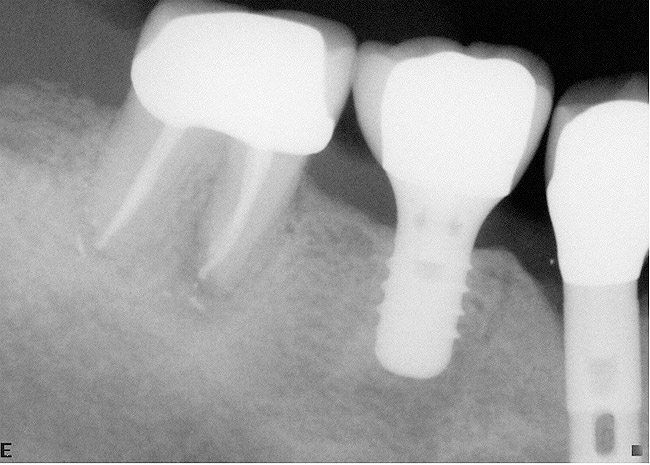

Case reports of these techniques can be seen in Figure 11 through Figure 19.

Figure 17  In another case, the mandibular left second molar was fractured and hopeless.

Figure 17

Figure 18  Following hemisection and extraction of the hopeless molar, implants were placed in the first and second molar positions, utilizing specific interradicular bone preparation techniques. Note the positioning of the implant in the second molar site so as to provide adequate dimension for ideal placement of an implant in the first molar area.

Figure 18

Figure 19  A radiograph taken after 46 months in function demonstrates the stability of the crestal peri-implant bone around both implants.

Figure 19